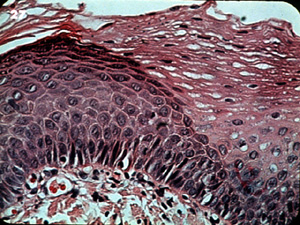

A más aumento se muestra la capa de

células basal muy activa, formando columnas y la capa de células

granular es prominente. Las células y núcleos son bastante uniformes. |